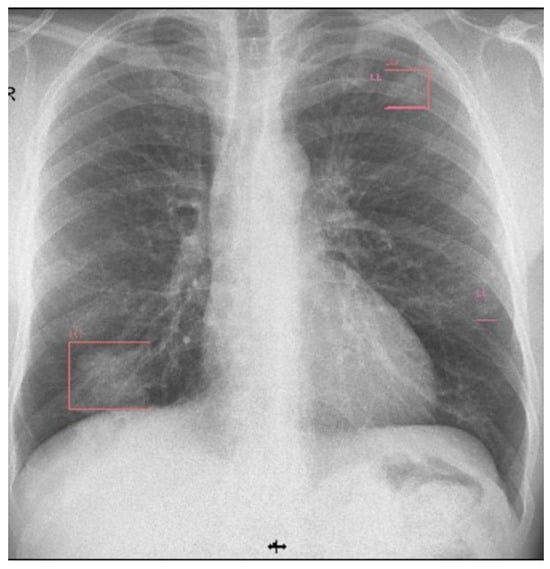

The patient was discharged after 58 days. The last chest X-ray was performed 8 weeks after being discharged (Figure 8).

Figure 8. Chest X-ray (8 weeks after discharge).